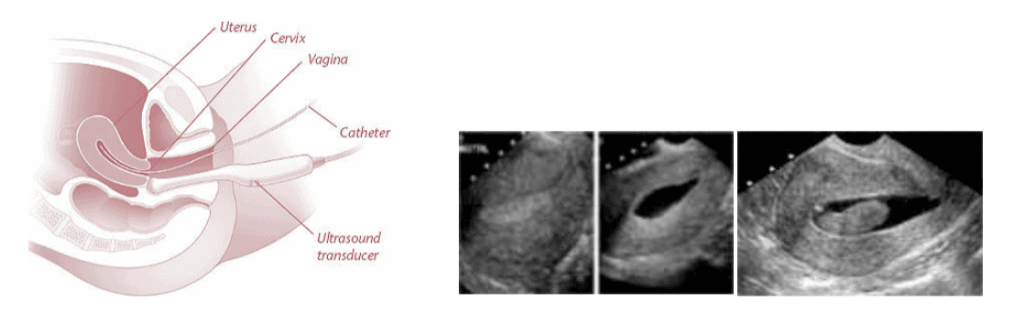

Ce este sonohisterografia?Este o procedură ecografică minim invazivă și eficientă care poate fi utilizată pentru a evalua imagistic cavitatea uterină și endometrul. Pentru a fi efectuată este necesară introducerea unui cateter mic prin canalul cervical în cavitatea endometrială prin intermediul căruia este introdusă soluție salină sterilă (ser fiziologic) și astfel se produce destinderea cavității uterine.

Ecografia este apoi efectuată prin tehnica transvaginală. Această metodă permite vizualizarea maselor comune asociate cu sângerarea uterină anormală, infertilitatea, avorturi recurente cum ar fi: Polipi endometriali; Leiomioame submucoase; Cheaguri sangvine intracavitare; Defecte congenitale uterine; Aderențe endometriale/ sinechii.

Această tehnică este dependentă de fazele ciclului menstrual și se efectuează ideal în faza proliferativă a ciclului menstrual pentru a reduce riscul rezultatelor fals pozitive sau negative, un endometru gros putând masca anumite formațiuni intracavitare.